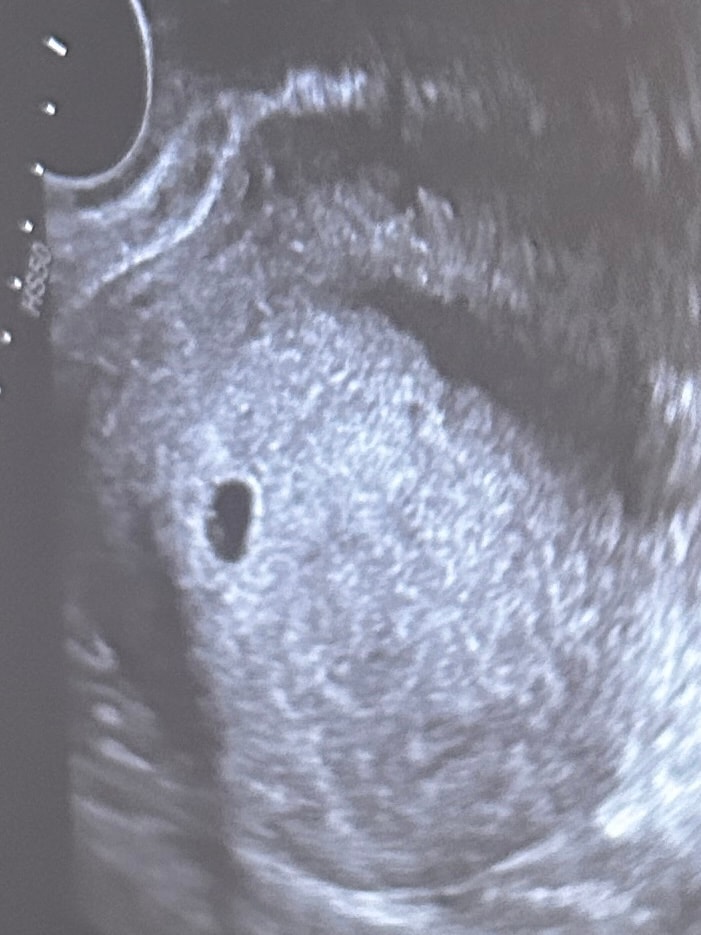

Не понимаю че такое, норма это или нет? Шейка на посл узи 35 (до установки была 20, сказали это пессарий так держит).